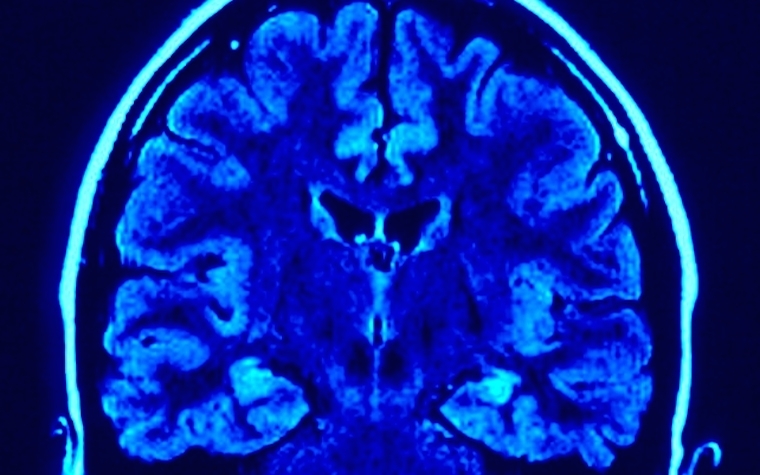

Beta waves (or rhythms) in the brain happen at 20 Hz frequency. Typically, these waves are connected to sensation, attention, and motion. These waves also show connections to Parkinson’s disease, among other illnesses. Researchers are unsure how these waves happen, whether they are because of an activity, or whether they have a significant purpose in the brain.

The researchers hypothesize that beta waves originate in the thalamus, which can send signals to dendrites on pyramidal neurons located in the cortex. Now the scientists want to determine whether the beta waves affect or reflect the brain’s health and behavior.